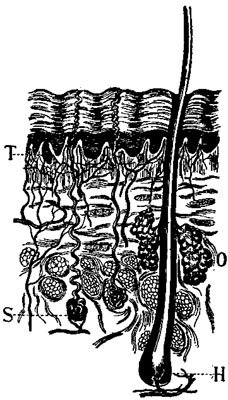

171 The Glands in the Skin

The Salivary Glands. Now, where does this saliva in the mouth come from? It is poured out from the pouches of the cheeks, and from under the tongue, by some little living sponges, or juice factories, known as salivary glands.[2]

In this diagram are shown the three glands (G) of the left side. The duct (D) from the parotid gland empties through the lining of the cheek; those from the lower glands empty at the front of the mouth under the tongue (T). N, nerve; A, artery; V, vein.